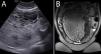

Las gestaciones gemelares de mola hidatiforme completa con feto normal son muy infrecuentes, con unos 300 casos reportados en la literatura. Este tipo de embarazos se consideran de alto riesgo obstétrico debido a las graves complicaciones maternofetales.

Los hallazgos clínicos y ecográficos pueden ser altamente indicativos de este tipo de gestaciones, pero el diagnóstico de certeza será habitualmente anatomopatológico. El diagnóstico diferencial de esta entidad suele incluir la mola parcial y los embarazos hidrópicos, que pueden presentar hallazgos similares, por lo que es importante tener claras las características morfológicas que nos pueden permitir diferenciarlas. Para esta tarea es muy útil el uso de la inmunohistoquímica para p57, aunque debemos tener en cuenta los casos con expresión aberrante de esta proteína.

Presentamos un caso de gestación gemelar de mola hidatiforme completa con feto vivo, con correlación radiopatológica, haciendo hincapié en el diagnóstico diferencial y la utilidad de la inmunohistoquímica para p57.